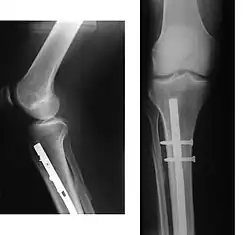

Эндопротезирование суставов

При наличии показаний к операции методом выбора может быть эндопротезирование суставов. В настоящее время разработаны и успешно применяются эндопротезы тазобедренного и коленного суставов. При остеопорозе эндопротезирование осуществляется конструкциями с цементным креплением. Дальнейшее консервативное лечение коленного сустава способствует снижению сроков реабилитации оперированных больных и повышению эффективности лечения.

Эндопротезирование тазобедренного сустава

Тазобедренный сустав — самый большой и сильно нагруженный сустав. Он состоит из головки бедренной кости, артикулирующей с вогнутой округлой вертлужной впадиной в кости таза. Показаниями к тотальному эндопротезированию тазобедренного сустава (ТЭТБС) являются патологические изменения, вызывающие стойкое нарушение функции с болевым синдромом и контрактурой. Целью тотального эндопротезирования тазобедренного сустава является уменьшение болевого синдрома и восстановление функции сустава. Данная операция является эффективным способом восстановления функции сустава, позволяющий значительно улучшить качество жизни человека. При ТЭТБС заменяется проксимальный отдел бедра и вертлужная впадина. Пораженные участки сустава заменяются на эндопротез, повторяющий анатомическую форму здорового сустава и позволяющий выполнять необходимый объём движений. В вертлужную впадину имплантируется ацетабулярная чашка. B дальнейшем подразумевается остеоинтеграция кости в компоненты протеза. В чашку устанавливается полиэтиленовая или керамическая вставка (оксид алюминия), называемая вкладышем. В бедро имплантируется ножка с конусом на шейке для крепления головки эндопротеза. Головка бывает керамической или выполненной из различных сплавов. Бедренный компонент (ножка) эндопротеза бывает цементной фиксации — и тогда крепится в бедре при помощи специального полимерного материала (костного цемента), а бывает бесцементной фиксации (pressfit) и как правило имеет пористое покрытие для возможности остеоинтеграции кости в компоненты протеза. Цементная фиксация более пригодна для пожилых людей. Различные пары трения (комбинации материалов различных компонентов) имеют различную выживаемость в теле человека. Так, например, самой успешной по выживаемости и самой имплантируемой системой, согласно ведущему независимому источнику Национальному Регистру эндопротезирования суставов Англии, Уэльса, Северной Ирландии и острова Мэн, является бесцементная ножка CORAIL® с бесцементной чашкой PINNACLE® (Johnson&Johnson, DePuy Synthes) c парой трения керамика-полиэтилен. Данная конструкция показывает выживаемость около 98 % за 10 лет наблюдений.

Риск осложнений при имплантации бесцементной ножки CORAIL® с бесцементной чашкой PINNACLE® с разными парами трения также наименьший[14].

Выделяют ряд осложнений — ятрогенный остеомиелит (нагноение), асептическое расшатывание компонентов протеза, различные сосудистые и неврологические нарушения. Нагноение бывает бактериологического плана (стрептококки, стафилококки и т. п.), вирусного (герпес), или грибкового и борются с ним соответствующими средствами — антибиотиками, противовирусными и противогрибковыми препаратами, особенно если конкретную причину удаётся выявить в результате пункций и посевов. При износе эндопротеза его полностью или частично заменяют новым, данная процедура называется ревизионным эндопотезированием сустава.